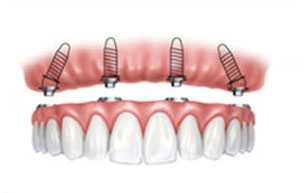

ALL-ON-4种植修复技术

种牙颗数少:只需4颗种植体就能够恢复半口牙,减少多颗种植费用。

适用范围广:对于长期缺牙导致牙槽骨萎缩严重的患者照样可以顺利种牙。

坚固耐用:四颗种植体抓力性好,术后的牙齿坚固程度和健康真牙一样。

自然美观:色泽和外观和真牙一样,完全可以以假乱真。

ALL-ON-4种植修复技术